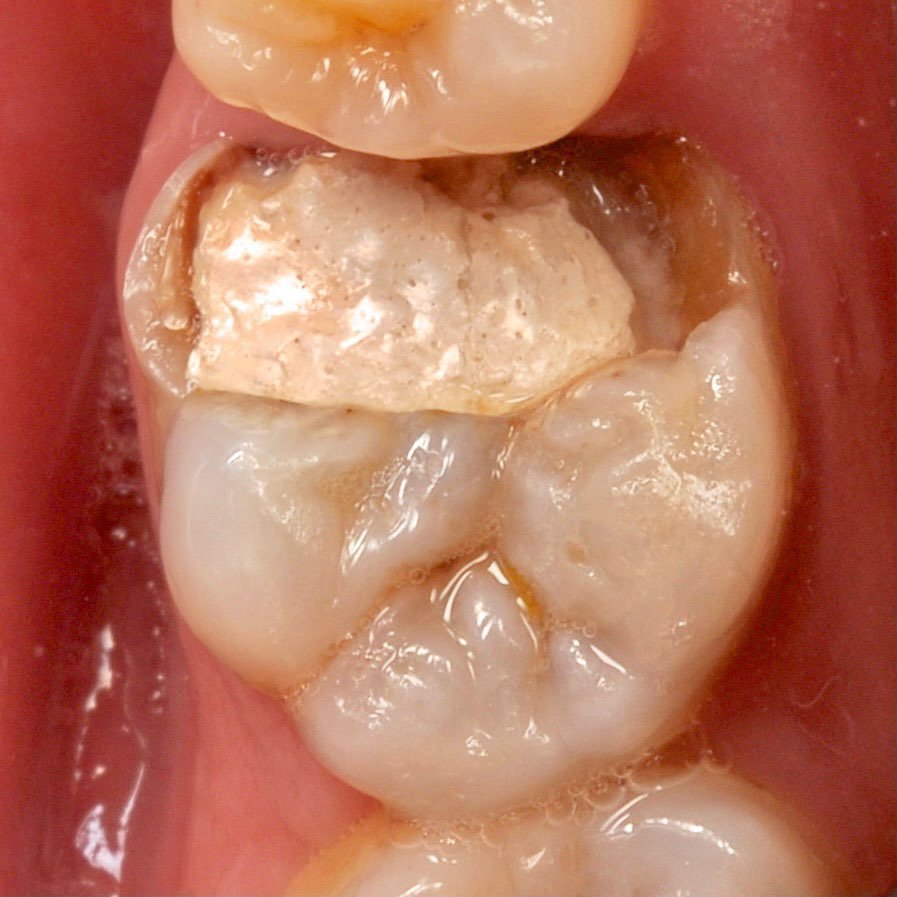

The use of a microscope in dentistry is an ultra-modern direction. Optical instruments allow for constant monitoring of the treatment process, which directly affects the quality of treatment and is aimed at preserving tooth tissues.

The microscope illuminates and enlarges the working field by about 25 times, which helps to accurately determine the anatomical structure of the tooth and restore it with maximum accuracy.

Successful endodontic treatment requires careful preparation, disinfection and sealing of the canals.

The most common complication encountered by the dentist during endodontic treatment is perforation and instrument breakage in the canal, resulting in the majority of patients losing a tooth. We can easily deal with such difficulties through a microscope.

Dental treatment under a microscope

Multiple increase

careful treatment of canals